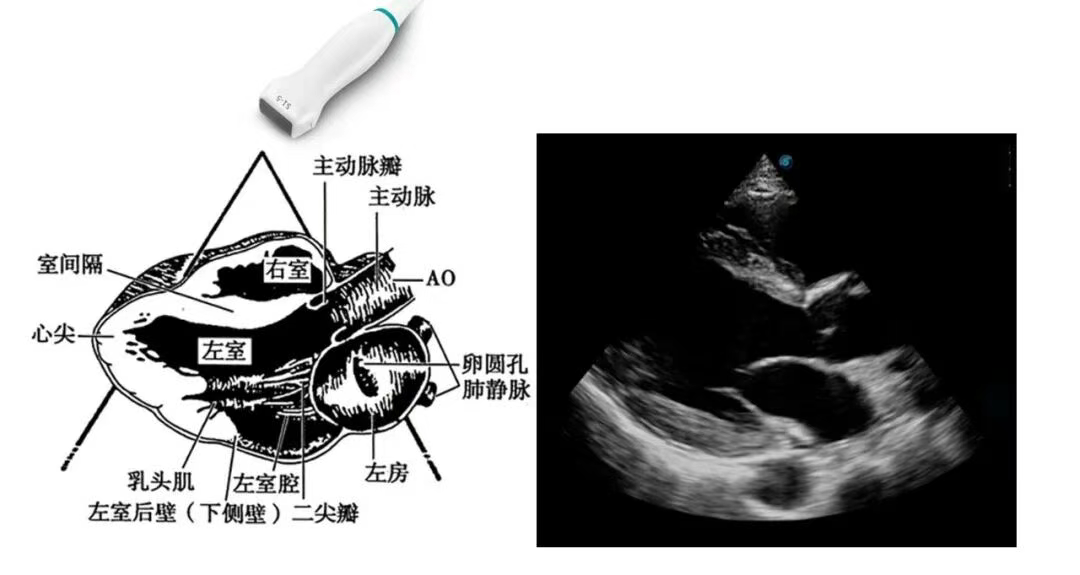

开立医疗联合武汉大学中南医院心血管病医院,将《心脏超声检查规范化中国专家共识 (2024版)》内容与实际临床工作需求融合,精心制作了指南挂图,助力标准采集,规范测量,期待这份实用且高清的工具,能成科室提升超声质效的助手!